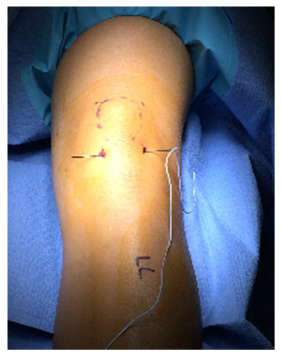

Four small incisions were made, each measuring 3-5mm. Two on either side of the proximal patella tendon or two more on either side of the distal quadriceps tendon. Labeled 1-4 (Figure 2). A large straight Keith needle was used to pass the suture starting from point 1 to 2, through the patella tendon at the inferior pole of the patella (Figure 3). The free suture end from point 2 is subcutaneously retrieved to point 3 with a Hewson suture passer (Smith and Nephew, Andover MA) (Figure 4). This free end of this suture is then passed from point 3 to 4 is with a straight Keith needle, through the quadriceps tendon at the superior pole of the patella. Finally, the other free suture end is retrieved from point 1 and delivered to point 4 (Figure 5). The free suture ends are then tensioned and tied at point 4 (Figure 6), completing the figure-of-8 tension band. A small tenotomy scissor was placed into each of the four incisions freeing the bursa from the tension band suture. Once all skin adhesions were clearly released, the four small incisions were closed, each with a single nylon suture.

Figure 3 Keith needle placing the suture through the proximal patella tendon, point 1 to 2.

Figure 4 Hewson suture passer subcutaneous retrieval of the free suture end from patella tendon, point 2, and delivering to the quadriceps tendon, point 3.